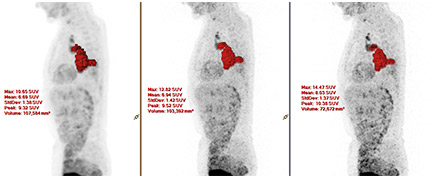

In a whole-body patient test study conducted by researchers at the University Hospital Salzburg, Austria, ×Sharp helped enhance the visualization of small lesions. Applying ×Sharp led to an increase in the lesion SUVmax compared with scans performed without ×Sharp. The lesions in the patients were in the 12-20 mm range.

Image courtesy of University Hospital Salzburg, Austria